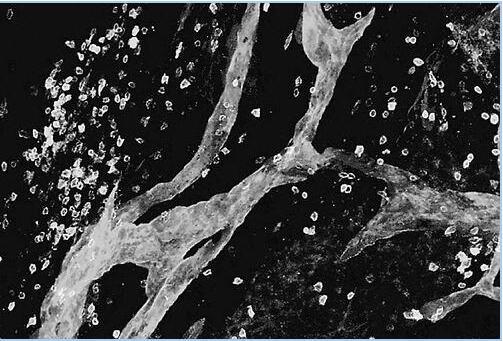

(大脑淋巴管的发现将打开神经性疾病研究新窗口)

对于认为已经绘制出人体系统的解剖学家来说,今年夏季的一项发现无疑像是发现了“新大陆”。一项出人意料的研究发现,淋巴系统——帮助清除体内废弃物以及运输免疫细胞的管道网络—— 一直延伸到大脑,而不是科学家一直以来认为的仅仅延伸到颈部。

两个多世纪以前,意大利物理学家Paolo Mascagni提出,大脑像人体其他部位一样也存在淋巴管道,今年,研究人员在探索小鼠大脑中免疫细胞的作用时,发现了大脑外皮层中组织精妙的T细胞。而附近的管道看起来像是在支配这些细胞,生物标记表明这些神秘的管道正是小鼠淋巴系统的延伸。此后,研究表明人类大脑中也有着类似的管道。

这些秘密管道藏在大脑最外层的脑膜中,可能有助于提供免疫系统和大脑如何互动的新见解。科学爱认为,大脑具有其自身的、与身体其他部位隔离的免疫系统。这项发现将有助于打开研究诸如阿尔茨海默氏症、多发性硬化和脑膜炎等神经退行性疾病和神经炎症的新窗口。但是现在,研究人员表示,他们优先考虑的是这些大脑淋巴系统的基础结构和功能。